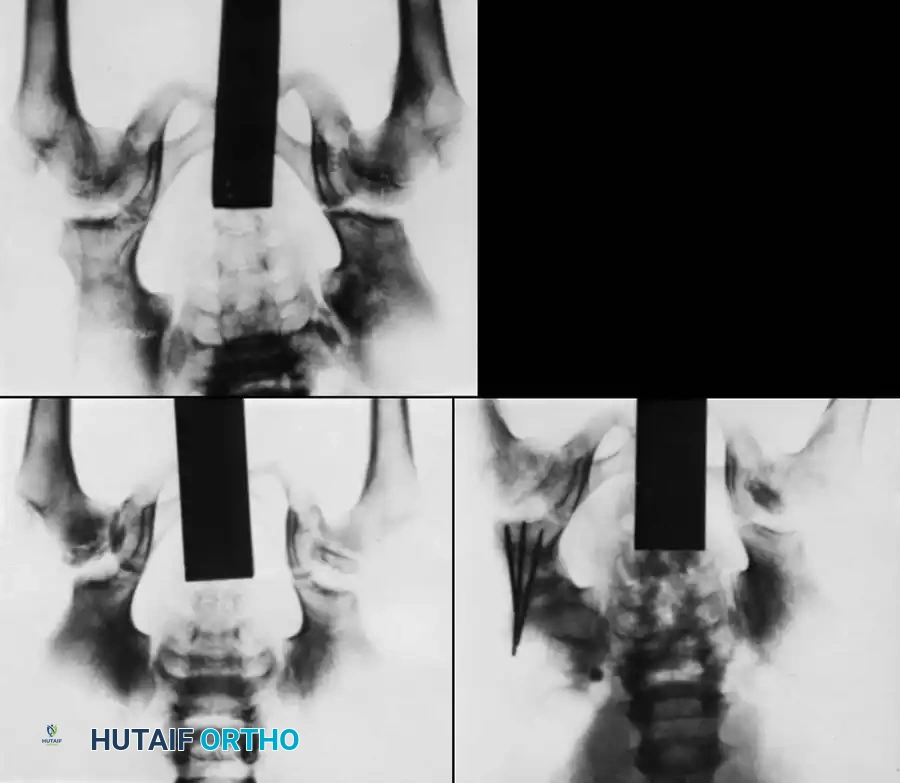

Plain Radiography:

Standard anteroposterior (AP) and frog-leg lateral radiographs of the pelvis remain the baseline. Early signs include a smaller ossification center, increased radiodensity (sclerosis), and widening of the medial joint space (Waldenström sign).

Salter and Thompson simplified early classification by measuring the extent of the subchondral fracture (crescent sign) in the superolateral femoral head on frog-leg lateral radiographs.

* Type A: Fracture line involves less than 50% of the superior dome (Good prognosis).

* Type B: Fracture line involves more than 50% of the superior dome (Fair/Poor prognosis, often requiring innominate osteotomy).

While Mukherjee and Fabry validated its accuracy, our institutional experience notes that subchondral fractures are visible early in only one-third of patients, limiting its universal application.

3. Herring Lateral Pillar Classification

The Herring classification is currently the most widely utilized and prognostically accurate system. It evaluates the height of the lateral pillar of the capital femoral epiphysis on an AP radiograph during the early fragmentation phase.